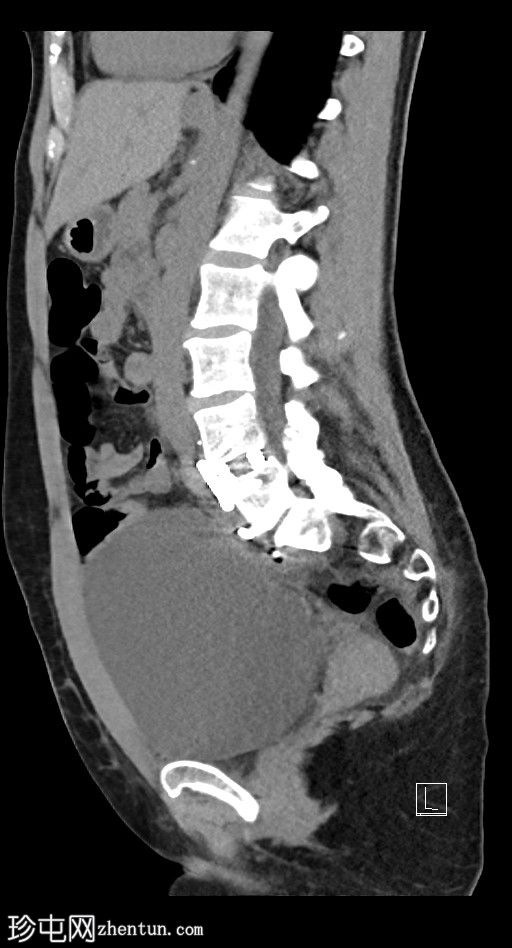

轴位

平扫

左侧腹膜后可见一巨大囊性肿块,位于左侧腰大肌内侧,紧邻多个手术夹(ALIF手术所用),这些手术夹紧贴囊性肿块后壁。

膀胱已行引流管减压,并被囊性肿块向右侧推移。

子宫和左侧附件在囊性肿块前方保持正常的脂肪间隙,因此附件囊性病变的可能性较小。

左侧输尿管难以辨认,因为它位于囊性肿块下缘后方。